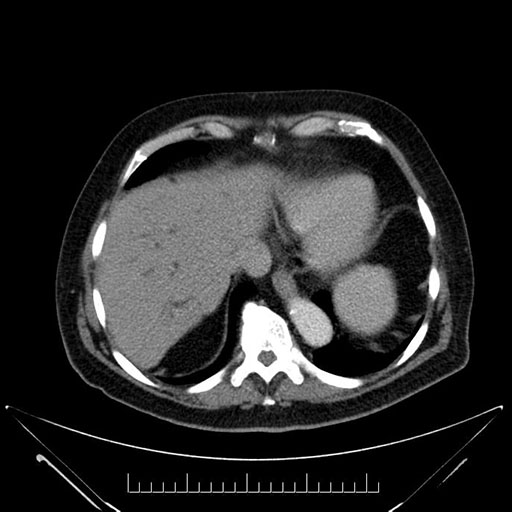

Imaging Analysis

Look through the patient's CT scan to identify any areas of concern for the necessary procedure.

Based on your CT findings, which issue(s) would give reason for "planned slowing down moment(s)" in this case?